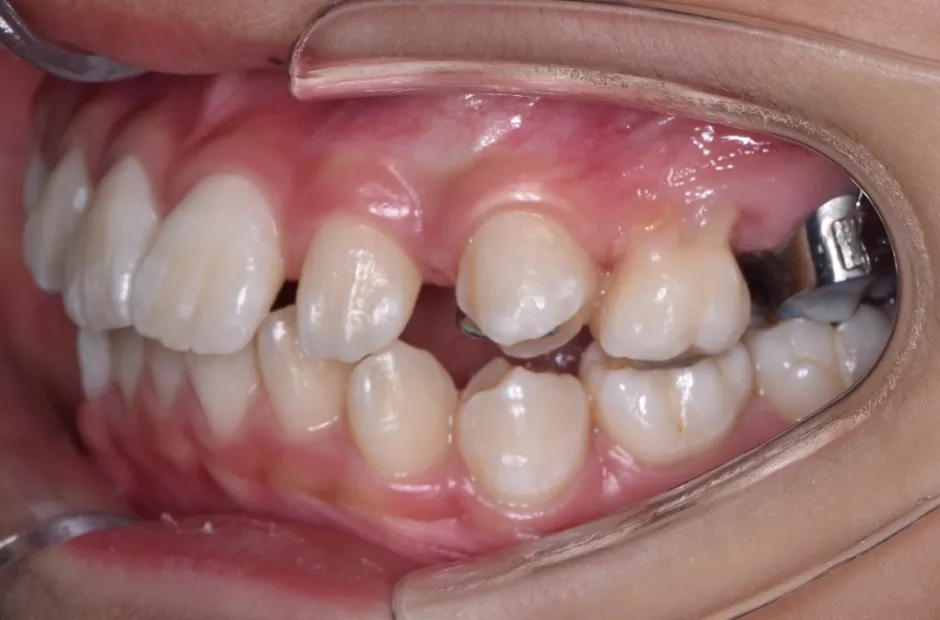

治療症例

ブラケット矯正

前歯部反対咬合

| 診断名・主訴 | 前歯部反対咬合 |

|---|---|

| 年齢・性別 | 14歳・男性 |

| 治療期間・回数 | 1年2か月 |

| 治療に用いた主な装置 | ブラケット矯正 |

| 抜歯部位 | なし |

| 治療費 | 60万円(税抜) |

| リスク・副作用 | 装置による違和感・疼痛・歯肉退縮・歯根吸収・虫歯のリスクなど |

治療前

治療中

治療後